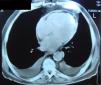

Dos exames complementares de diagnósticoNo estudo do nosso doente aplicámos então as novas modalidades ecocardiográficas, nomeadamente a determinação do strain do VE e o estudo da velocidade longitudinal do anel mitral em protodiástole (E’). Verificámos que o strain longitudinal do VE estava mantido, assim como a velocidade protodiastólica do anel mitral (E’ septal: 8,4cm/s; E/E’: 8,3) (Fig. 1), apresentando uma variação respiratória > 25%. Pelo contrário, o strain circunferencial estava reduzido, achados que corroboravam a hipótese de PC. À semelhança do exame realizado 11 anos antes, a TC do tórax documentou a existência de espessamento regular do pericárdio, desta vez com focos visíveis de calcificação pericárdica. Não se verificaram alterações pleuroparenquimatosas significativas (Fig. 2). Também a ressonância magnética (RM) cardíaca confirmou a existência de espessamento pericárdico, ligeiro, localizado às paredes ventriculares basais e medianas, atingindo na parede lateral do VE cerca de 3mm (normal < 2mm). Os volumes ventriculares e a FEj. do ventrículo direito eram normais. A FEj. do VE foi quantificada em 40% (moderadamente reduzida) e a insuficiência mitral era ligeira. Não foi efetuado estudo de realce tardio, por ausência de colaboração do doente na progressão do exame.

Ainda relativamente ao diagnóstico desta entidade, a TC do tórax e RM cardíaca detetam um pericárdio espessado, mas são meios de diagnóstico que providenciam informação meramente anatómica e não refletem necessariamente a alteração fisiopatológica presente5. No caso apresentado, estes dois exames apoiaram a nossa principal hipótese, documentando um pericárdio espessado, com focos de calcificação. No entanto, é importante lembrar que 18% dos doentes com PC comprovada cirurgicamente poderão apresentar um pericárdio normal e, portanto, a ausência de espessamento não refuta a hipótese de PC6.